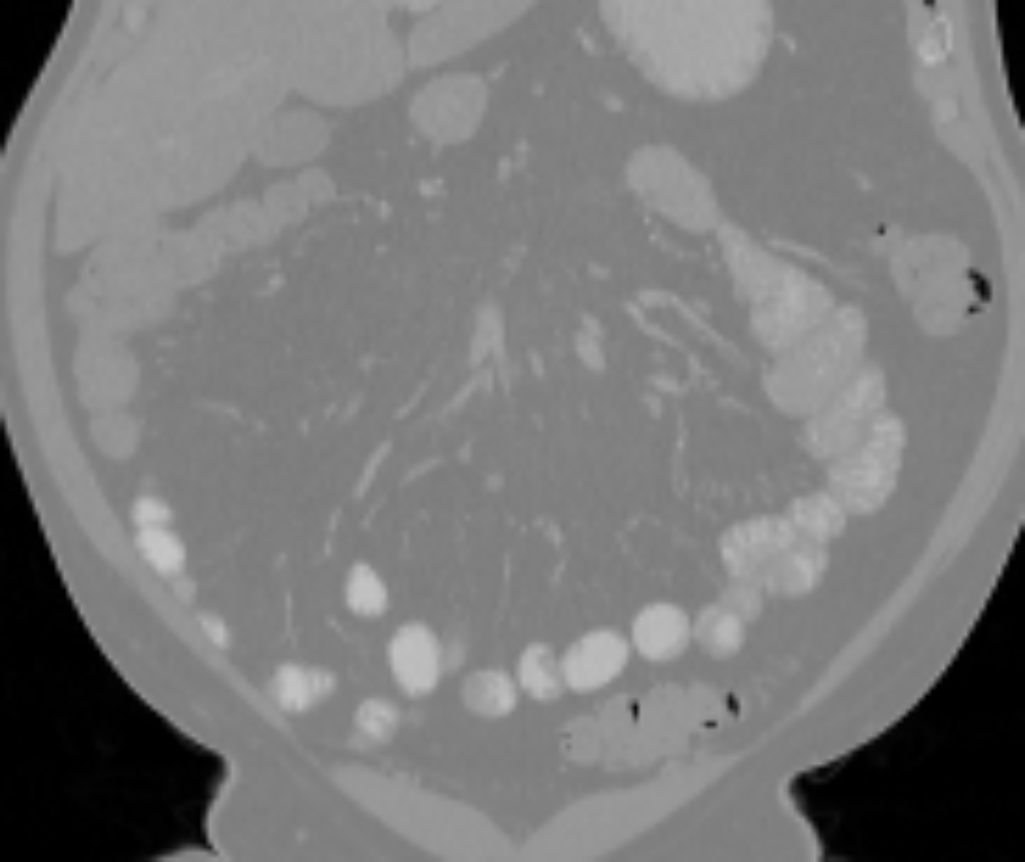

The small bowel has a cylindrical shape but also has many touchings with different parts along its path, which makes it have variable topologies across patients and time. It is inappropriate to apply a constant topological constraint to such organs. Fig. 1 shows an example of the small bowel path covered by the lumpy ground-truth (GT) segmentation.

GT labels were achieved by an experienced radiologist using 3DSlicer111https://www.slicer.org [6] based on the following steps. Firstly, the path of the small bowel is drawn as interpolated curves which connect a series of manually placed points inside the small bowel. Secondly, we grow the curves using a margin of and threshold it again using a Hounsfield unit (HU) range of . Manually drawn air pockets, which have much lower HU values, are also added during the second step. Produced errors are manually fixed in the final step. We note that this annotation procedure took one or two full days for each volume. Finally, the dataset includes the two types of labels, which are the path and segmentation of the small bowel as shown in Fig. 1.

Fig. 3 shows example segmentation results. The proposed method eliminates false positives on the large bowel by the help of the applied topological constraint. Fig. 4 further clarifies the effectiveness of the proposed method by presenting 3D rendered segmentations. The proposed method produces a more topologically correct segmentation of the small bowel with fewer false positives. Fig. 5 presents example barcode diagrams, which again show the reduced numbers of connected components and holes within the segmentation result of the proposed method.